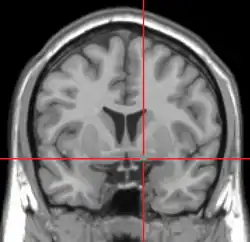

![]() MRI showing a coronal plane of the head with marks showing the location of the substantia innominata, the region in which the nucleus basalis is found. | |

The nucleus basalis in humans is a somewhat diffuse collection of large cholinergic neurons in the basal forebrain.[2] The main body of the nucleus basalis lies inferior to the anterior commissure and the globus pallidus, and lateral to the anterior hypothalamus in an area known as the substantia innominata.[1] Rostrally, the nucleus basalis is continuous with the cholinergic neurons of the nucleus of the diagonal band of Broca.[1] The nucleus basalis is thought to consist of several subdivisions based on the location of the cells and their projections to other brain regions.[2] Occasional neurons belonging to the nucleus basalis can be found in nearby locations such as the internal laminae of the globus pallidus and the genu of the internal capsule.[1]